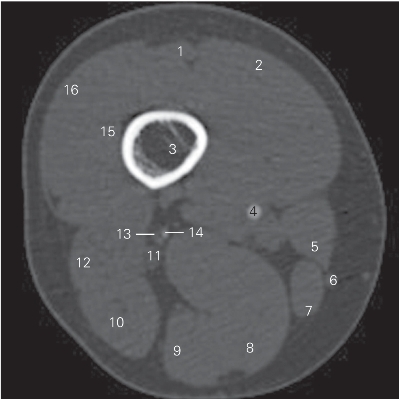

图5-9 经股骨下份的横断层CT图像(骨窗)

1 股直肌 rectus femoris 2 股内侧肌 vastus medialis

3 股骨 femur 4 股动脉 femoral artery

5 缝匠肌 sartorius 6 大隐静脉 greater saphenous vein

7 股薄肌 gracilis 8 半膜肌 semimembranosus

9 半腱肌 semitendinosus 10 股二头肌长头 long head of biceps femoris

11 坐骨神经 sciatic nerve 12 股二头肌短头 short head of biceps femoris

13 股静脉 femoral vein 14 股深动脉 deep femoral artery

15 股中间肌 vastus intermedius

16 股外侧肌 vastus lateralis